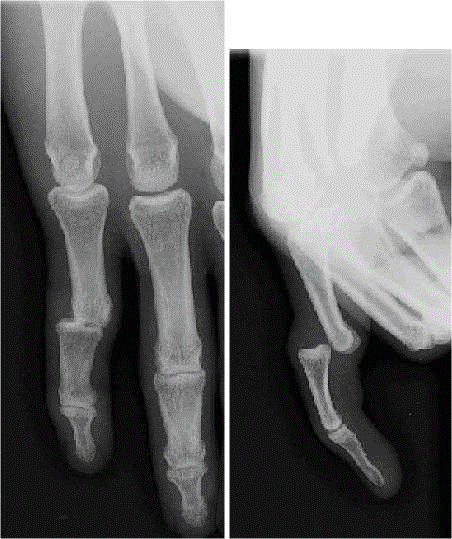

- – QUELQUES IMAGES PATHOLOGIQUES

LUXATION DE L’ARTICULATION INTER-PHALANGIENNE PROXIMALE

FRACTURE D’UNE PHALANGE

FRACTURE DE LA BASE DU 5ième METACARPIEN